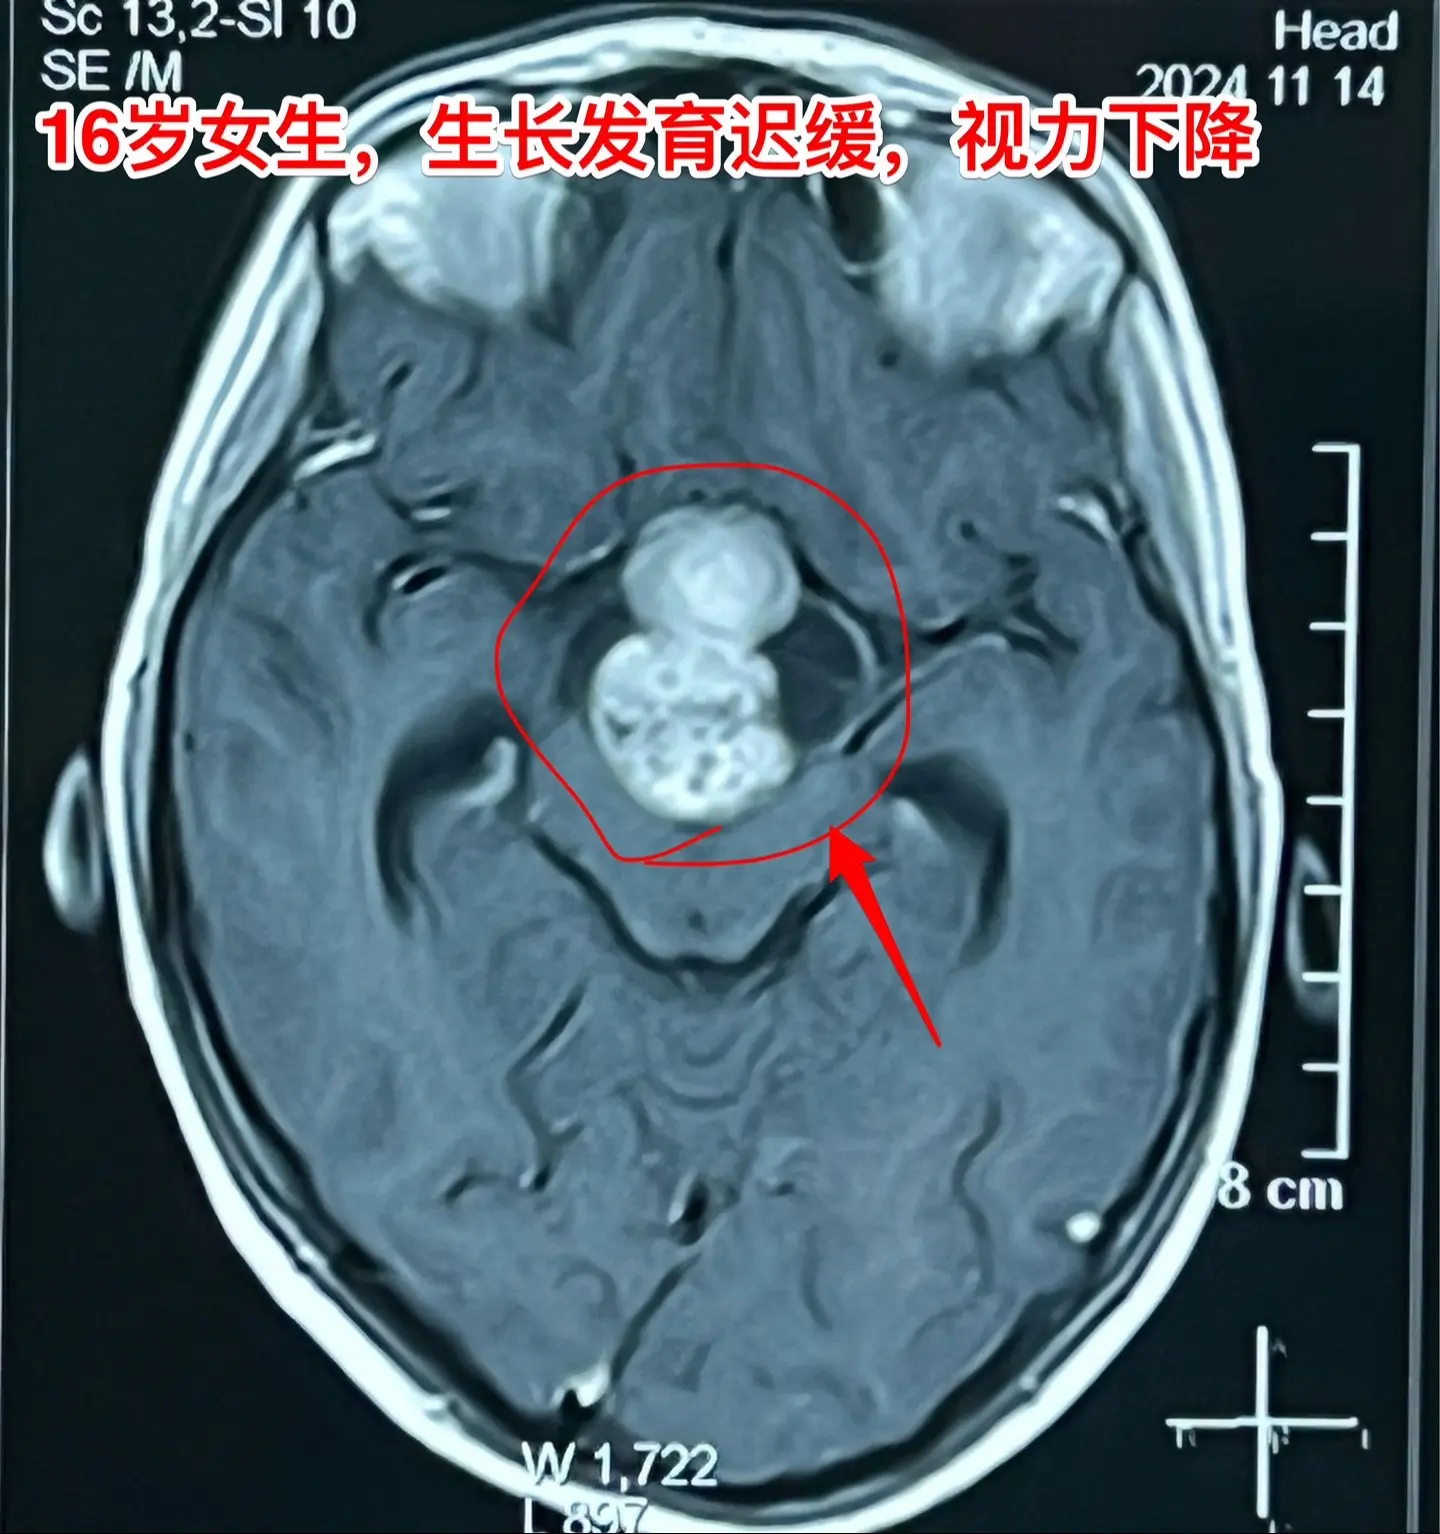

16岁女生在10岁时就有生长发育迟缓症状。16岁衡阳市女生,现在身高才120厘米,体重才21公斤。初中毕业后就辍学了! 她在10岁时就有生长发育迟缓症状,到医院去检查发现生长激素分泌不足。没有找出具体原因,也没有注射生长激素治疗。 近一年有头痛症状,视力也下降了。作磁共振发现长了脑部肿瘤,才到北京来找我作手术。肿瘤体积大,没有钙化,是颅咽管瘤吗? 昨天在手术过程中,取出病变标本作快速冰冻病理检查,报告为乳头型颅咽管瘤。这种类型的颅咽管瘤在小孩子中十分罕见。 我多次提醒家长,如果发现小孩子的生长发育有异常,要尽早到医院去检查,找出原因,尤其是针对脑部要作磁共振检查,排除脑部肿瘤。对于生长激素缺乏者,不能不管原因,轻易注射生长激素治疗。